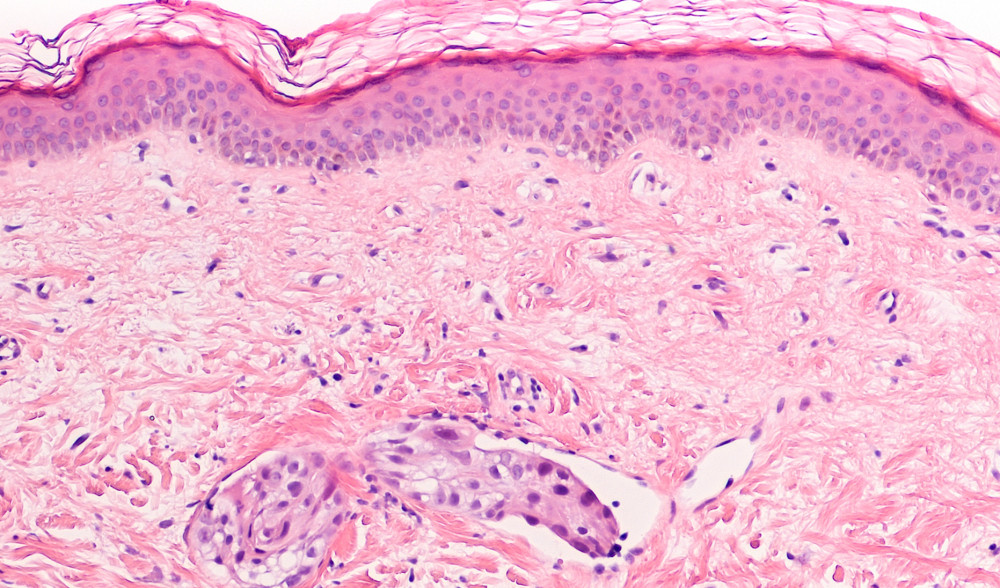

Geni in grado di prevedere il rischio individuale di sviluppare metastasi a distanza di tempo, per alcuni dei tumori al seno più diffusi tra le donne. Li ha scoperti un gruppo di ricercatori dell'Istituto Europeo di Oncologia (IEO) e dell’Università statale di Milano guidati da Pier Paolo Di Fiore e Salvatore Pece, docenti di Patologia generale. La firma molecolare, in sostanza, consentirà di personalizzare trattamenti e terapie mediche e chirurgiche in base alle caratteristiche della singola paziente: i set di geni individuati nella nuova firma molecolare sono soprattutto quelli coinvolti in un tipo di tumore al seno molto diffuso, il Luminal B.

I risultati della ricerca, pubblicati sulla rivista scientifica EBioMedicine del gruppo “The Lancet”, indicano in venti geni specifici quelle ‘sentinelle’ che consentono di misurare la staminalità presente nel tumore primario.

I parametri utilizzati finora hanno il problema di guardare alle caratteristiche dell’intera massa tumorale invece che alla rara sottopopolazione di cellule staminali tumorali che si nasconde all’interno dei tumori. Cosa che invece avviene con la firma molecolare staminale individuata dai ricercatori, il cui studio è stato sostenuto dall’Associazione italiana per la Ricerca contro il Cancro (AIRC).